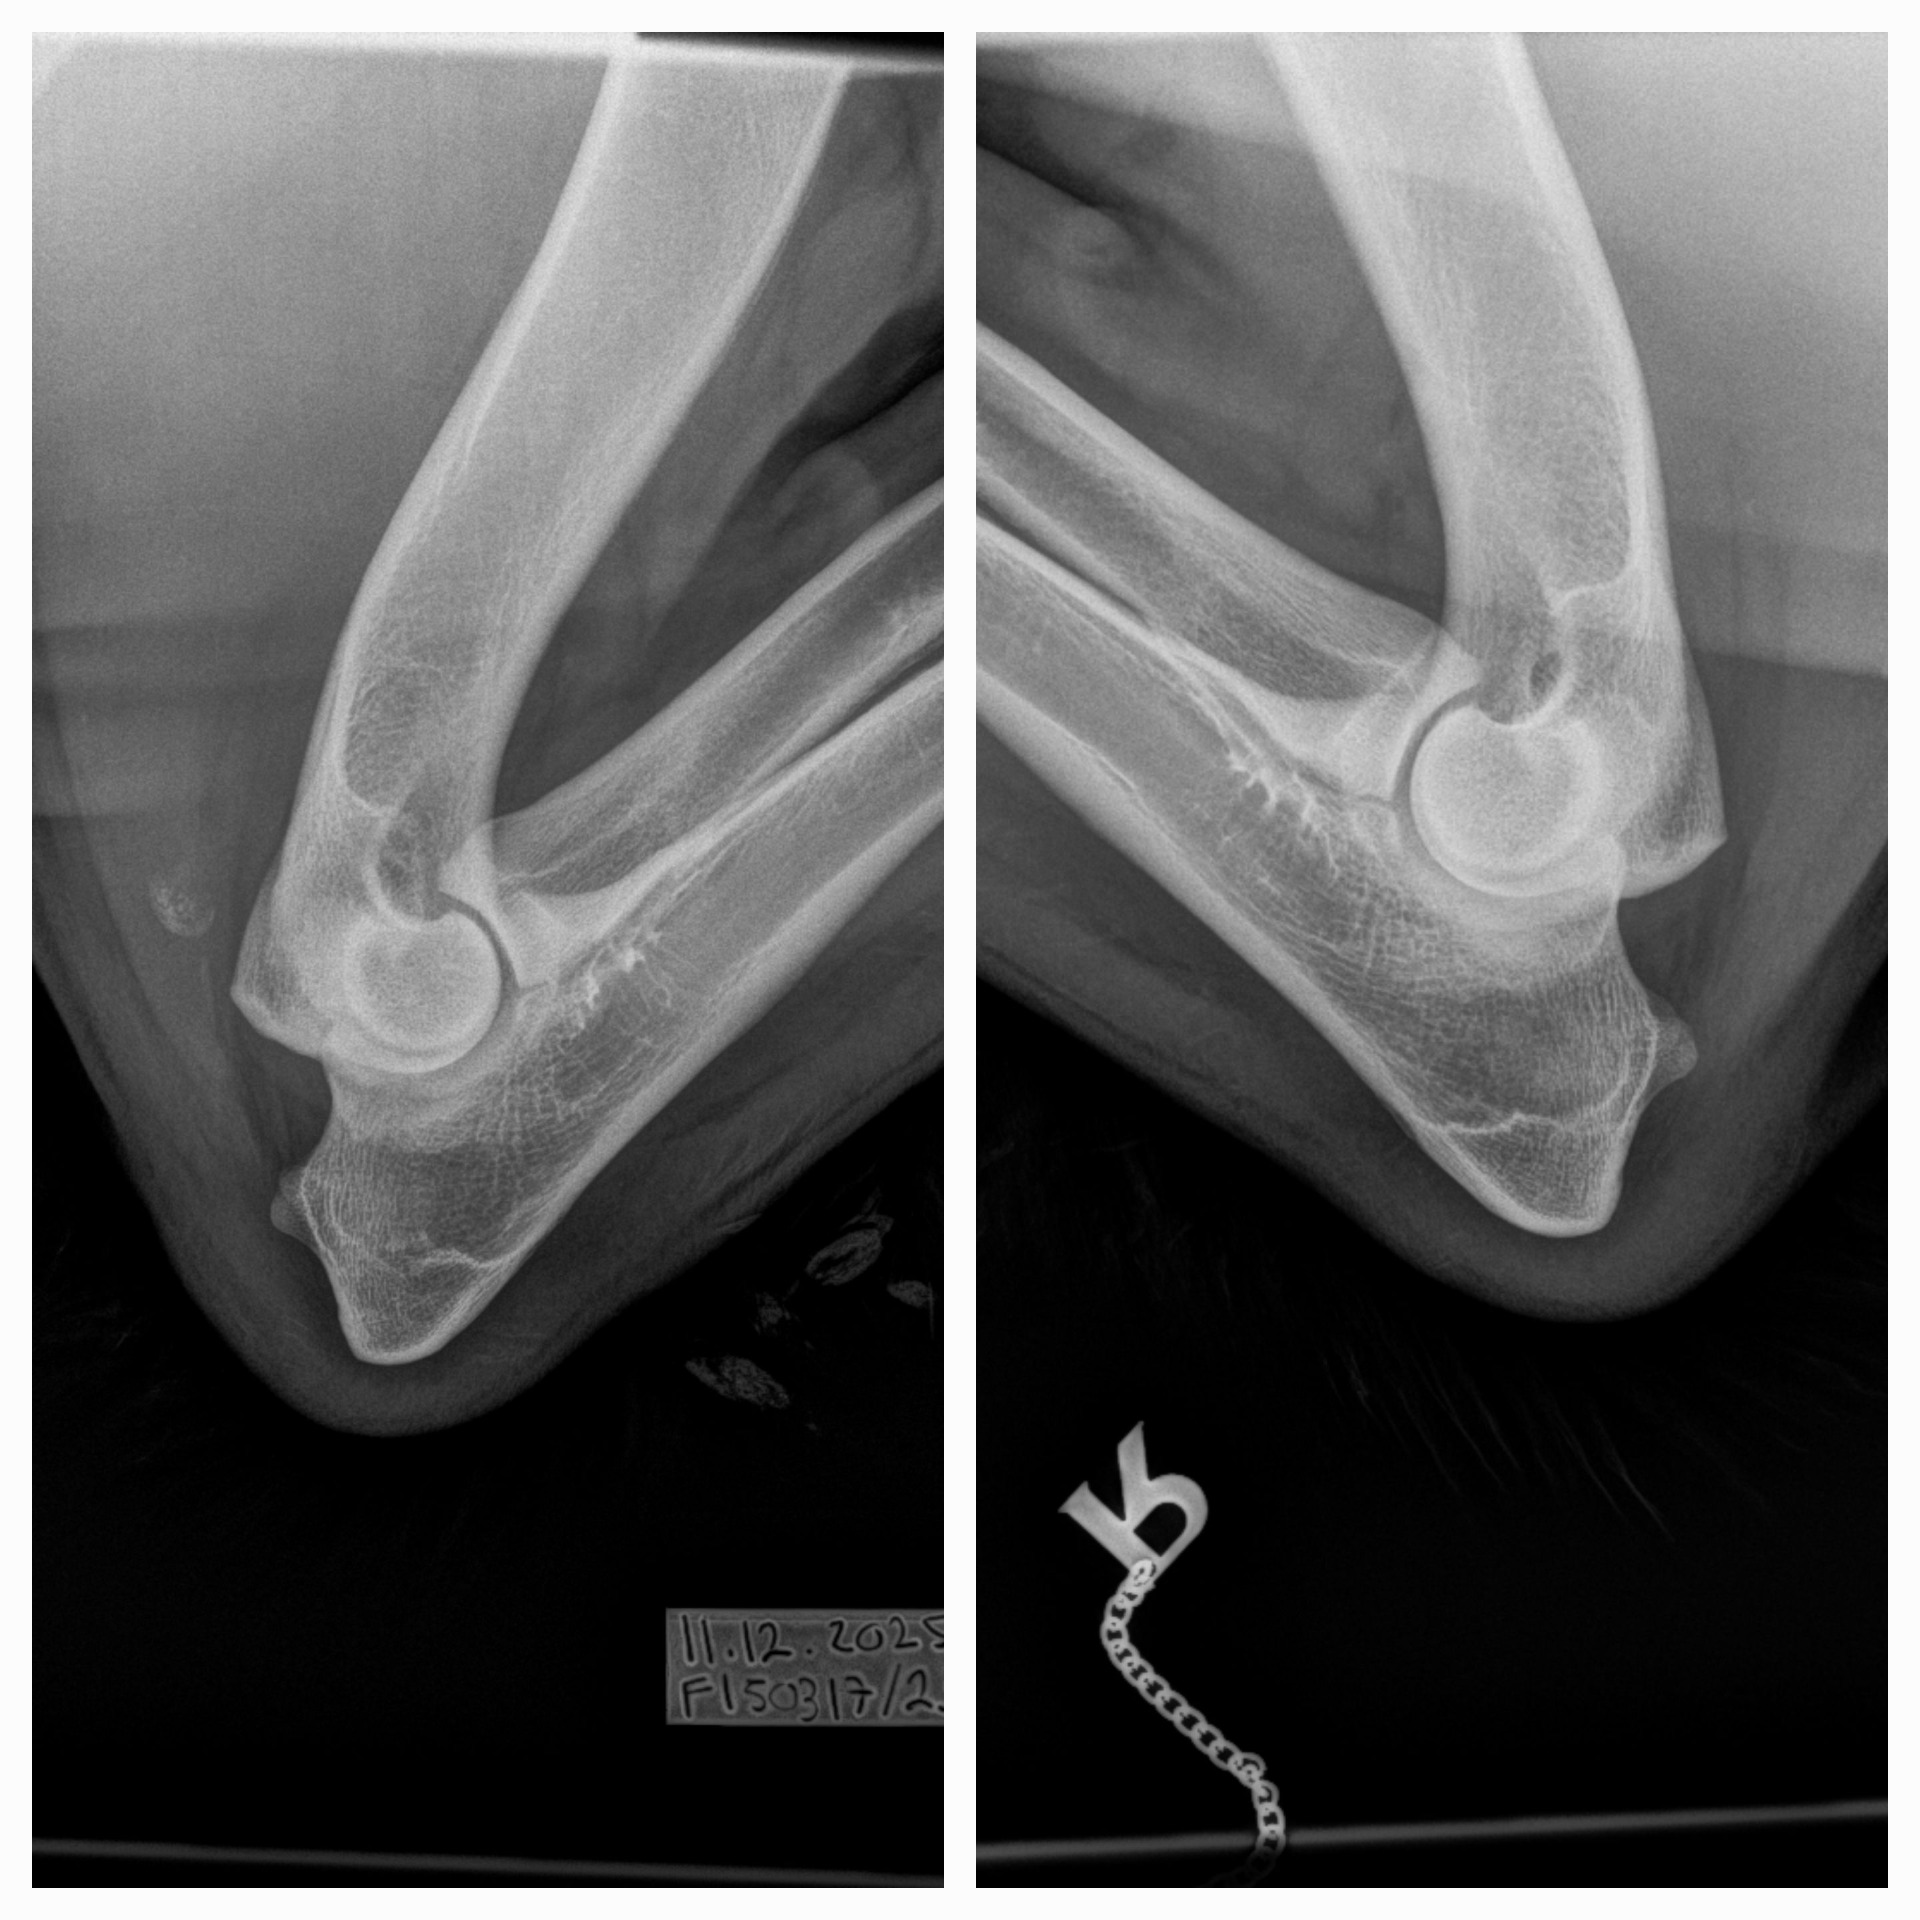

| 12.12.2025 | kyynärniveldysplasia lonkkaniveldysplasia | 0/0 D/D |